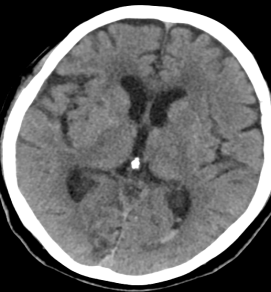

近日,常德市第二人民医院神经外科收治了一名神志昏迷2+小时的脑出血老年女性患者。面对“脑出血”这一诊断,患者家属表现出极大的担忧与无助。患者是否还有救?康复后能否正常生活?应采取保守治疗还是手术治疗?若选择手术,微创或开颅哪种更为适宜?这些问题都落在了负责该患者的管床医生、主治医师蔡英波的肩上。在安抚家属情绪的同时,蔡英波明确表示:“您母亲目前的情况必须手术。根据入院CT结果,我们可以选择微创手术治疗。”

(患者发病时头部CT)